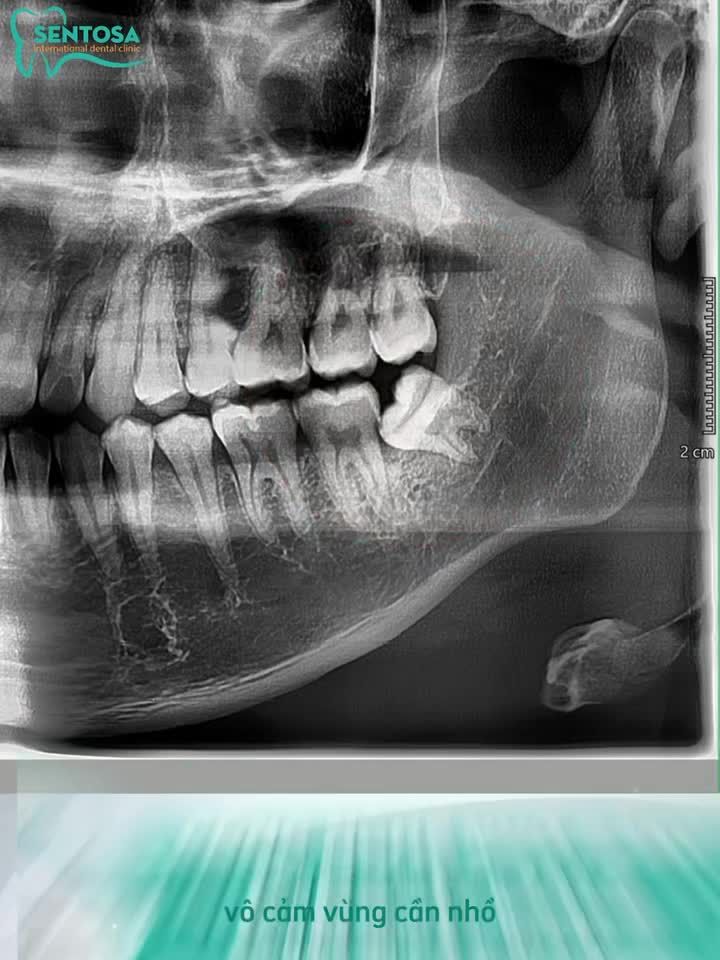

Nhổ răng khôn mọc lệch má, sâu vỡ thân răng cho chị Phương - Sentosa chi nhánh Thái Nguyên.